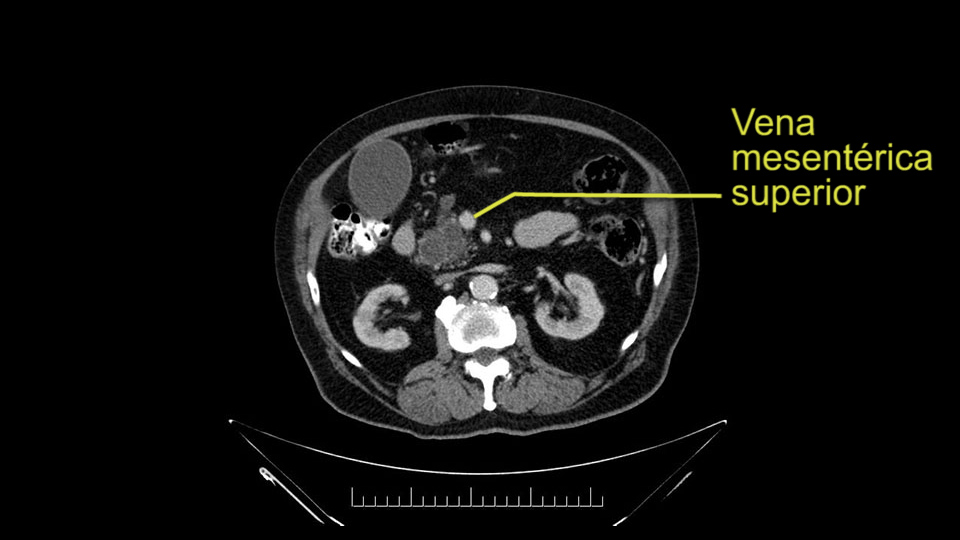

The next item that I would look at: the issue would be the vessels and usually start at the portal vein, watch the portal vein, follow it down, down-down-down to the neck of the pancreas - which is here - and there’s no impingement by tumor, which is great. The SMV and the splenic vein, which is here. The splenic vein junction is normal, which is great.

Then look at the first jejunal branch - which is this thing here - this little branch which goes under the SMA. It’s something that we’ve just started appreciating over the past few years and the reason for that is: there’s two or three small branches that come out of the uncinate into the the first jejunal and it’s a fairly inevitable part of the operation where there’s some bleeding. As long as you’re cognizant of what’s happening, it’s no reason to panic and that kind of bleeding will eventually stop or can be stopped but it’s not easy because these little vessels are fragile from the uncinate to the first jejunal. So I do focus on that and it’s pretty consistent I’d say 9 times out of 10, people have that first jejunal.

In planning for my further steps, the first key that I find, first do a gentle mobilization of the hepatic flexure of colon completely away because that’s going to help me do a good wide Kocher maneuver. Why do I slow down? Because there are small tributaries and small blood vessels which communicate between the transverse mesocolon and the head of the pancreas and you also have the loop of Henle all the blood vessels which drain into the superior mesenteric vein just as it gets underneath the neck of the pancreas.

The initial hepatic flexure mobilization and the Kocher procedure is then going to enable me to understand the uncinate process of this patient, which should not be a problem, again. But the initial pictures had shown a degree of touching. I would not even say involvement or abutment; a degree of touching with the superior mesenteric vein. So that would give me an early chance to assess how the superior mesenteric vein is in this patient. So this would be the initial slowing down moment.

The next thing we always evaluate, although we do not expect invasion to the portal veins in this case, we must always trace the path of the portal vein, in both directions, from top to bottom. The splenoportal confluence and the superior mesenteric vein, which in this case does not appear to be compromised.

Por otro lado, siempre evaluamos -aunque en este caso no esperamos que haya invasión de los vasos portales-, siempre hay que hacer el recorrido de la vena porta, en ambos sentidos, de arriba hacia abajo; el confluente esplenoportal y la vena mesentérica superior, que en este caso no aparentan estar comprometidos.

The first steps of a pancreaticoduodenectomy involve ensuring the CT findings are correct: exploring for signs of metastatic disease, peritoneal implants involving the omentum or the undersurface of the diaphragm and if again this is confirmed exploration that there's no metastatic disease, I begin the mobilization and really determining the relationship of the tumor with the major visceral vessels. I start by an extended Kocher maneuver, identify the superior mesenteric vein below the neck of the pancreas. They’re very thin walled vessels and as you're dissecting you have to use the ultimate care and meticulously dissect the superior mesenteric vein, ligate the anterior branches and begin the dissection from below to under the neck of the pancreas. At this point, if there's no reason to be concerned about whether there is any vascular invasion below, I usually take the gallbladder down. I mobilize the common hepatic duct above the insertion of the gallbladder. This patients already has a stent in place. So I would divide the bile duct at this point. This facilitates the dissection of the anterior surface of the portal vein and as I would expect looking at this imaging that there is nothing to be concerned about in terms of vascular involvement.